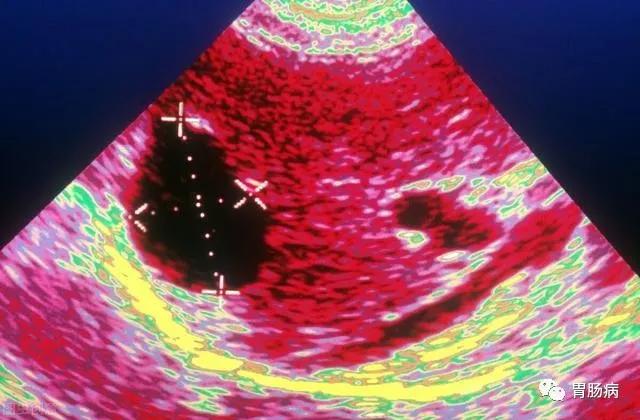

超声是最有效的初检手段,如果需要进一步鉴别,可以再做CT或者核磁共振,甚至穿刺针吸活检等检查。CT如下图所示

囊肿小的,可以1-2年复查一次彩超,囊肿比较大的,半年到1年复查一次为妥。